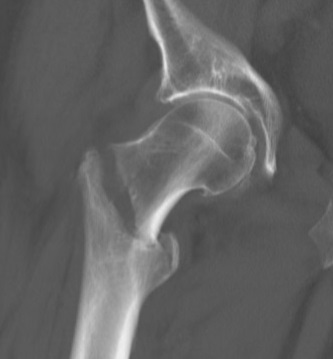

- 고관절 골절

가장 치명적입니다. 대수술이 필요하며, 연세가 많거나 건강 상태가 좋지 않으면 수술조차 어려운 경우도 있습니다. 이 경우 집에서 앉거나 누워 지내다가 2년 이내 사망률이 급격히 증가합니다.